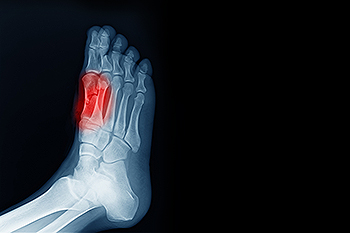

The forefoot is the front part of the foot that contains ligaments, tendons, muscles, nerves, blood vessels, metatarsal bones, and phalanges. The metatarsal bones are the five long bones between the toe bones, the hindfoot, and the midfoot. There are a variety of conditions that can lead to forefoot pain, including Morton’s neuroma, toe pain, and sesamoiditis. The focus here is on sesamoiditis. Most bones are connected to other bones at joints. Sesamoids are bones embedded in muscle and only connected to tendons. On the bottom of the foot, near the big toe, two small sesamoids help with weight bearing and raising the bones of the big toe. Sesamoiditis happens when these tendons become irritated and inflamed. This is common among runners and dancers. If you suffer from pain in your forefoot, it is suggested that you visit a podiatrist to determine the cause of the pain, whether it’s sesamoiditis, and how to treat it best.

Sesamoiditis is a condition of the foot that affects the ball of the foot. It is more common in younger people than it is in older people. It can also occur with people who have begun a new exercise program, since their bodies are adjusting to the new physical regimen. Pain may also be caused by the inflammation of tendons surrounding the bones. It is important to seek treatment in its early stages because if you ignore the pain, this condition can lead to more serious problems such as severe irritation and bone fractures.